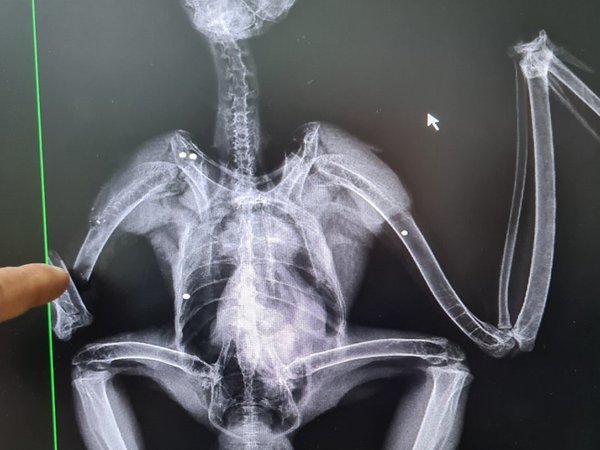

Το Διπλοσιάχινο, το οποίο βρέθηκε στο δάσος Μαχαιρά και παραδόθηκε στην Υπηρεσία Θήρας και Πανίδας, έφερε τραυματισμό στη φτερούγα, ο οποίος, όπως επιβεβαιώθηκε από την ακτινογραφία, προκλήθηκε από πυροβολισμό κυνηγετικού όπλου. Το πουλί χειρουργήθηκε και λαμβάνει την απαραίτητη φροντίδα στο Κέντρο Περίθαλψης και Αποκατάστασης της Άγριας Πανίδας της ΥΘΠ μέχρι να είναι έτοιμο να απελευθερωθεί στη φύση και πάλι.

Το Διπλογέρακο, από την άλλη, το οποίο βρέθηκε στην Αυδήμου, δεν φάνηκε τόσο τυχερό, αφού άφησε την τελευταία του πνοή λίγα λεπτά μετά από τον εντοπισμό του. Αν και η αιτία θανάτου δεν έχει εξακριβωθεί, η ακτινογραφία κατέδειξε επίσης σκάγια σε διάφορα σημεία του σώματος του. Η Υπηρεσία Θήρας και Πανίδας και ο Πτηνολογικός καλούν τους πολίτες να καταγγέλλουν τέτοια περιστατικά, ώστε οι παρανομούντες να αντιμετωπίζουν τις συνέπειες των πράξεων τους, για να μην την «πληρώνουν» ούτε η άγρια ζωή, ούτε οι ευσυνείδητοι κυνηγοί.